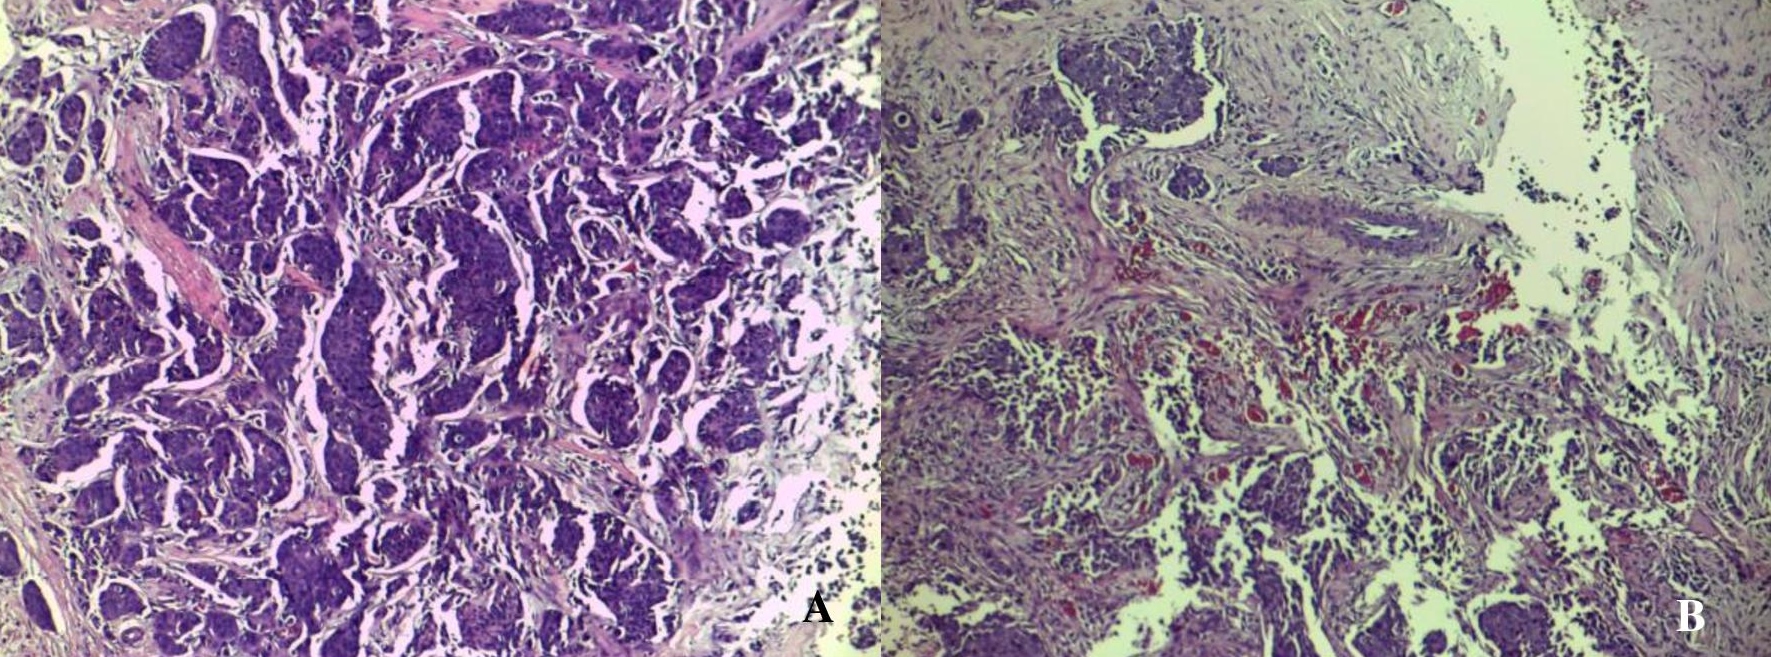

Figure 2. Histopathologic features of the high-density mass seen in the right breast of the patient discloses invasive ductal carcinoma. (A) Seen are neoplastic ductal structures infiltrating the surrounding structures including the adjacent adipose tissue (H&E, 40x). (B) Other areas prominently show the formation of new blood vessels amidst clusters of tumor cells with associated extensive desmoplasia (H&E, 100x).

Figure 4. Microscopic appearances of the core biopsy taken from the enhancing left breast mass identified in the patient showing invasive ductal carcinoma. The tumor is very cellular and is composed of neoplastic cells disposed in tongues, cords and groups with attempts to form ducts (A). Note the pronounced desmoplastic reaction, which adds to the density seen radiographically. Some areas of the lesion reveal an abundance of well- and newly-formed blood vessels (B) (H&E, 100x).